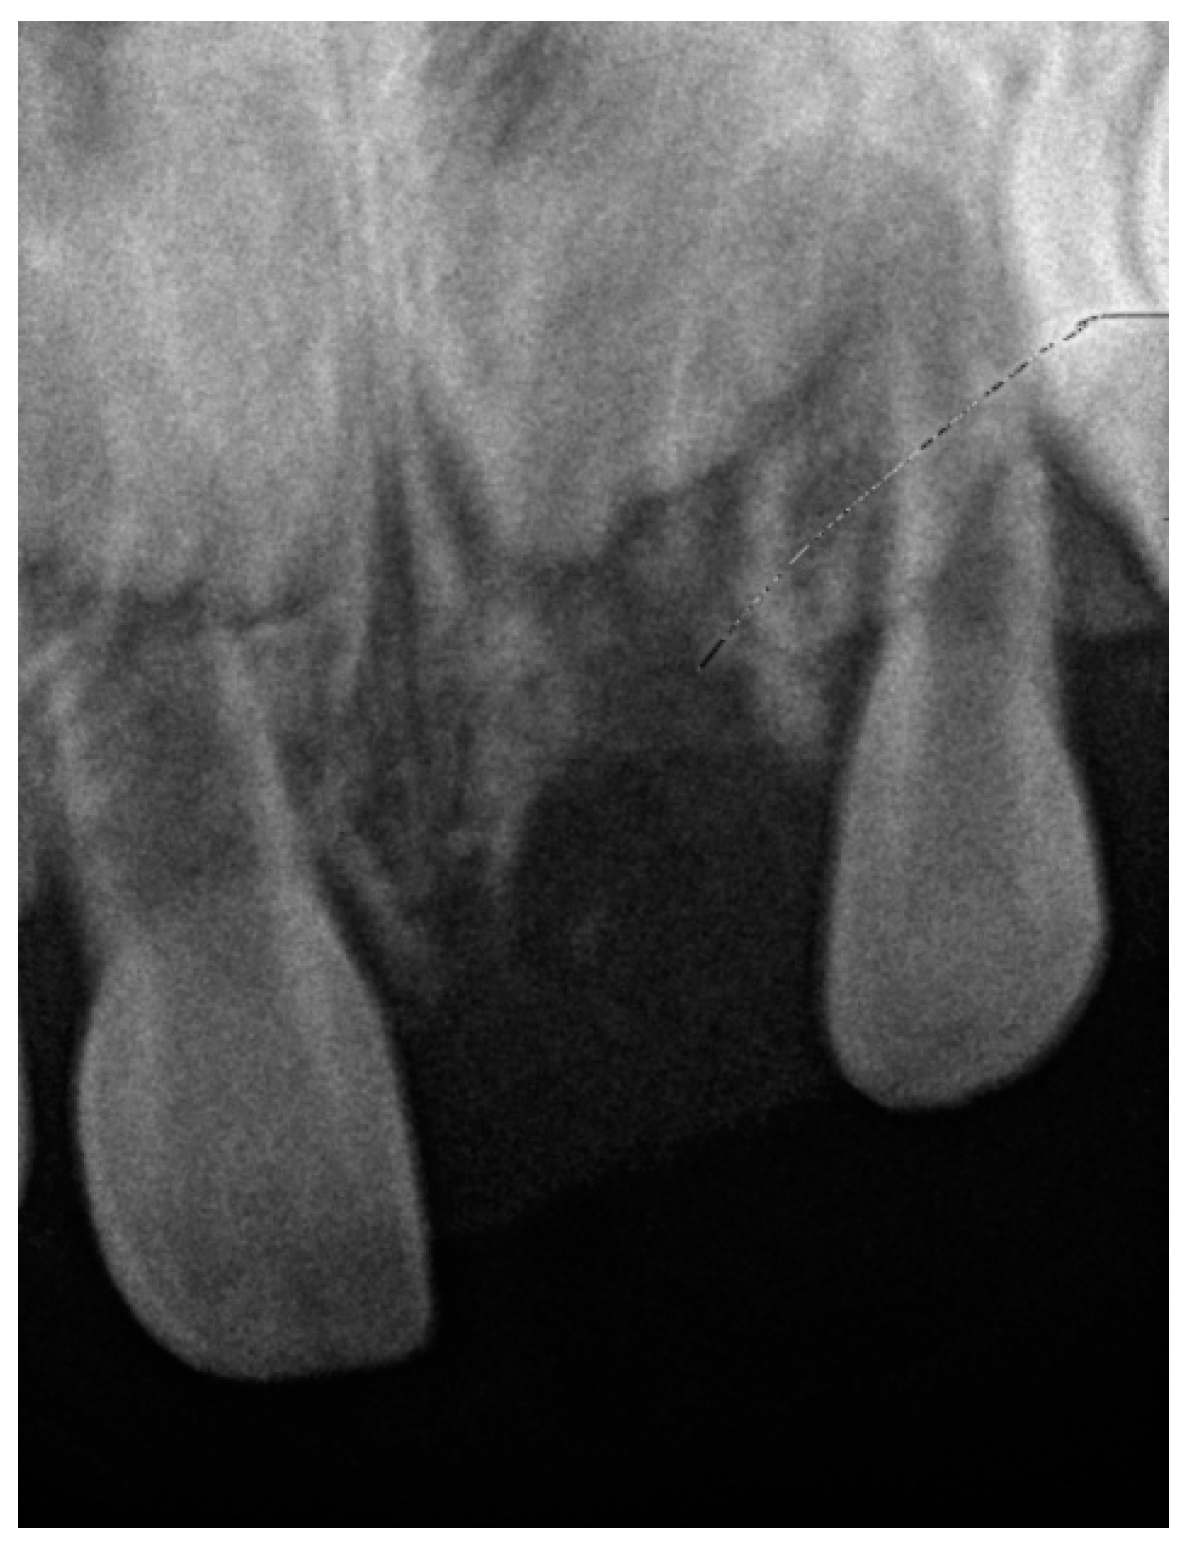

2. Case Presentation